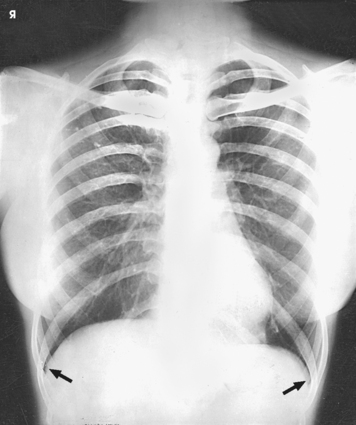

The lungs are the organs of respiration (Fig. 10-4). They are the mechanism for introducing oxygen into the blood and removing carbon dioxide from the blood. The lungs are composed of a light, spongy, highly elastic substance, the parenchyma, and they are covered by a layer of serous membrane. Each lung presents a rounded apex that reaches above the level of the clavicles into the root of the neck and a broad base that, resting on the obliquely placed diaphragm, reaches lower in back and at the sides than in front. The right lung is about 1 inch (2.5 cm) shorter than the left lung because of the large space occupied by the liver, and it is broader than the left lung because of the position of the heart. The lateral surface of each lung conforms with the shape of the chest wall. The inferior surface of the lung is concave, fitting over the diaphragm, and the lateral margins are thin. During respiration, the lungs move inferiorly for inspiration and superiorly for expiration (Fig. 10-5). During inspiration, the lateral margins descend into the deep recesses of the parietal pleura. In radiology, this recess is called the costophrenic angle (see Fig. 10-5, B). The mediastinal surface is concave with a depression, called the hilum, that accommodates the bronchi, pulmonary blood vessels, lymph vessels, and nerves. The inferior mediastinal surface of the left lung contains a concavity called the cardiac notch. This notch conforms to the shape of the heart.

Fig. 10-5 A, Movement of lungs during inspiration and expiration. B, Costophrenic angles shown (arrows) on PA projection of chest.